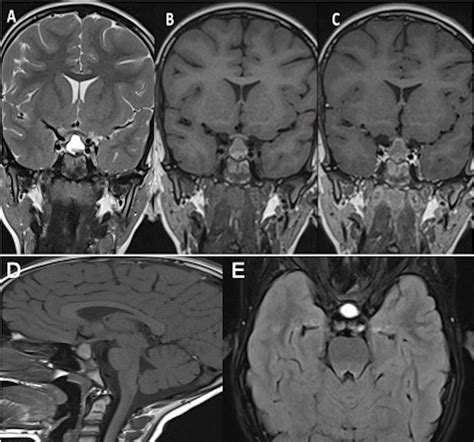

Diagnosing disorders related to the Pouch of Rathke involves a combination of clinical evaluation, imaging studies, and laboratory tests. Imaging techniques such as magnetic resonance imaging (MRI) and computed tomography (CT) scans are commonly used to visualize the pituitary gland and detect any abnormalities. Laboratory tests measure hormone levels to assess pituitary function and identify any hormonal imbalances.

• rathke cleft cyst pictures

• rathke cleft cyst radiopaedia

• rathke pouch cyst

• rathke's cleft cyst pictures